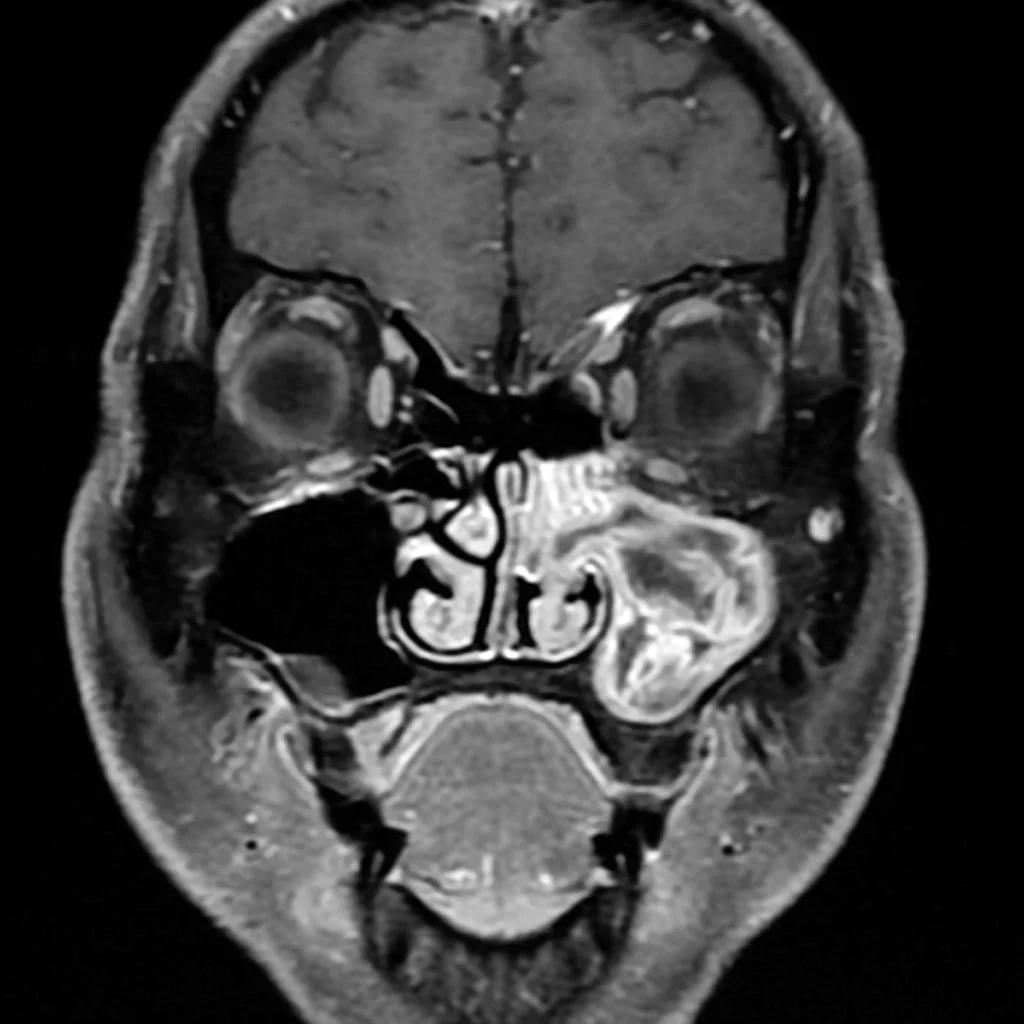

• Convoluted cerebriform pattern (alternating stripes of high and low intensity on MR)

• T1: Isointense to muscle, heterogenous enhancement

• T2: hyperintense to muscle

• Non-cancerous sinonasal mass that rarely has malignant transformation

• Presentation/Imaging

• Typically middle aged men

• Lateral wall of nasal cavity most commonly

• Bony remodeling